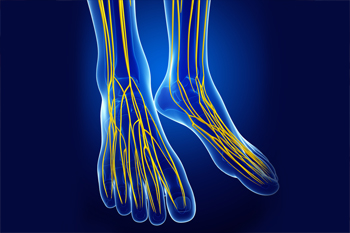

Symptoms of Lower Limb Peripheral Neuropathy

Peripheral neuropathy is a condition in which one or more nerves of the peripheral nervous system are damaged. This often affects the lower limbs and may involve multiple nerves (polyneuropathy) or only one nerve (mononeuropathy). A single nerve may be damaged due to a sudden injury, prolonged pressure on the nerve, a local compression, or inflammation. Multiple nerves may be damaged due to systemic diseases, such as diabetes. The symptoms of peripheral neuropathy in the lower limbs include numbness, prickling, or tingling in the toes, burning, freezing, throbbing, or shooting pains, sensitivity to touch, and muscle weakness. If you are experiencing the symptoms of peripheral neuropathy in your feet or ankles, please seek the care of a podiatrist.

Neuropathy

Neuropathy can be a potentially serious condition, especially if it is left undiagnosed. If you have any concerns that you may be experiencing nerve loss in your feet, consult with one of our doctors from Texas. Our doctors will assess your condition and provide you with quality foot and ankle treatment for neuropathy.

What Is Neuropathy?

Neuropathy is a condition that leads to damage to the nerves in the body. Peripheral neuropathy, or neuropathy that affects your peripheral nervous system, usually occurs in the feet. Neuropathy can be triggered by a number of different causes. Such causes include diabetes, infections, cancers, disorders, and toxic substances.

Symptoms of Neuropathy Include:

- Numbness

- Sensation loss

- Prickling and tingling sensations

- Throbbing, freezing, burning pains

- Muscle weakness

Those with diabetes are at serious risk due to being unable to feel an ulcer on their feet. Diabetics usually also suffer from poor blood circulation. This can lead to the wound not healing, infections occurring, and the limb may have to be amputated.

Treatment

To treat neuropathy in the foot, podiatrists will first diagnose the cause of the neuropathy. Figuring out the underlying cause of the neuropathy will allow the podiatrist to prescribe the best treatment, whether it be caused by diabetes, toxic substance exposure, infection, etc. If the nerve has not died, then it’s possible that sensation may be able to return to the foot.

Pain medication may be issued for pain. Electrical nerve stimulation can be used to stimulate nerves. If the neuropathy is caused from pressure on the nerves, then surgery may be necessary.

Neuropathy

Neuropathy is a condition in which the nerves in the body become damaged from a number of different illnesses. Nerves from any part of the body, including the foot, can be damaged. There are several forms of neuropathy including peripheral neuropathy, cranial neuropathy, focal neuropathy, and autonomic neuropathy. Furthermore there is also mononeuropathy and polyneuropathy. Mononeuropathies affect one nerve while polyneuropathies affect several nerves. Causes of neuropathy include physical injury, diseases, cancers, infections, diabetes, toxic substances, and disorders. It is peripheral neuropathy that affects the feet.

The symptoms of neuropathy vary greatly and can be minor such as numbness, sensation loss, prickling, and tingling sensations. More painful symptoms include throbbing, burning, freezing, and sharp pains. The most severe symptoms can be muscle weakness/paralysis, problems with coordination, and falling.

Podiatrists rely upon a full medical history and a neurological examination to diagnose peripheral neuropathy in the foot. More tests that may be used include nerve function tests to test nerve damage, blood tests to detect diabetes or vitamin deficiencies. Imaging tests, such as CT or MRI scans, might be used to look for abnormalities, and finally nerve or skin biopsies could also be taken.

Treatment depends upon the causes of neuropathy. If the neuropathy was caused by vitamin deficiency, diabetes, infection, or toxic substances, addressing those conditions can lead to the nerve healing and sensation returning to the area. However if the nerve has died, then sensation may never come back to the area. Pain medication may be prescribed for less serious symptoms. Topical creams may also be tried to bring back sensation. Electrical nerve stimulation may be used for a period of time to stimulate nerves. Physical therapy can strengthen muscle and improve movement. Finally surgery might be necessary if pressure on the nerve is causing the neuropathy.

If you are experiencing sensation loss, numbness, tingling, or burning sensations in your feet, you may be experiencing neuropathy. Be sure to talk to a podiatrist to be diagnosed right away.